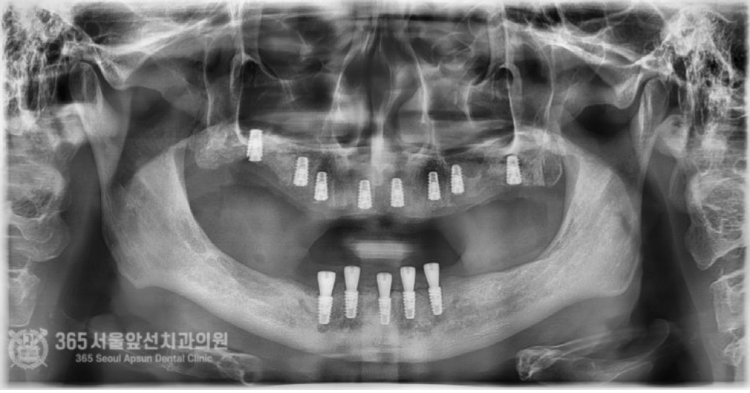

안녕하세요. 주안동치과 365서울앞선치과의원입니다. 오늘 소개할 증례의 환자분은 위아래 턱뼈가 극단적으로 없었던 환자분입니다. 근처 치과를 돌고 돌다 도저히 치료가 불가능하다고 판정 받았는데 지인분의 소개로 저희 주안동치과에 내원하게 되었던 분입니다. 환자분께서는 치료가 가능할지 걱정이 많으셨는데, 간단하게 답변드렸습니다. 뼈가 없으면 만들면 되고, 신경이 있으면 피하면 됩니다. 걱정은 저희가 할테니 환자분께서는 걱정하실 필요없겠습니다 ㅎㅎ 촬영일시 : 2024.07.03. 처음 내원하셨던 당시 파노라마 엑스레이 사진입니다. 위턱의 치아들이 전체적으로 흔들리고 당장 손가락으로 뽑아도 뽑힐 지경의 상황입니다. 또한 양쪽 상악동 부위의 잔존골이 거의 없으며, 상악동 천공 양상도 관찰됩니다. 아래턱의 경우는 더욱 심각합니다. 일단 과도한 골흡수로 어금니 부위에는 임플란트 식립 자체가 불가능할 정도의 뼈 상태입니다. 위턱의 치아들을 발치하고 뼈를 만들어 주면서 상악동 거상술을 동반하여 동시에 임플란트를 심어드렸습니다. 아래턱의 경우는 신경관이 위치하고 있기 때문에 신경관의 위치를 파악하여 정교하게 신경을 피해서 임플란트를 식립하였습니다. 위쪽, 아래쪽 모두 수술 난이도는 최상에 속한다고 보시면 되겠습니다. 촬영일시 : 2024.10.03. 수술이 완료되고 체크 과정에서 찍은 파노라마 엑스레이 사진입니다. 반듯하게 정확한 위치에 임플란트들이 위치되었습니다. 이렇게 반듯하게 식립된 임플란트를 보면 기분이 편안해집니다 ㅎㅎ 경험이 있는 의사라면 네비게이션 수술 혹은 수술용 가이드의 도움 없이 눈으로 보고 심더라도 가이드 보다 더 정확하게 수술이 가능합니다 ㅎㅎ 촬영일시 : 2024.12.02. 수술 후 체크 과정에서 잇몸의 상태입니다. 깨끗하게 낫고 있습니다ㅎㅎ 보철물의 제작은 디지털 방식을 통해 진행됩니다. 디지털 방식을 통해서 정밀한 보철물 디자인이 가능합니다.